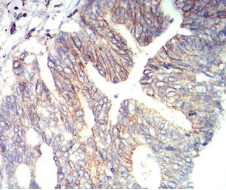

IHC    1/200 - 1/1000